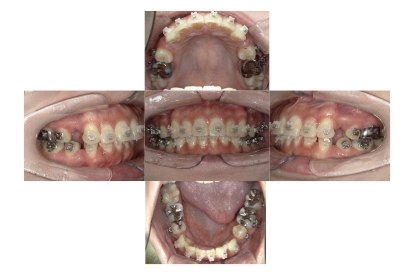

BEFORE

治療経過

AFTER

上下顎叢生(上下の前歯のガタガタ)のケースです。

装置はラビアル(上下表側)で、上下顎の小臼歯を4本抜歯を行っています。抜歯したスペースを使って、上下の前歯の後方移動と叢生(ガタガタ)の改善を行っています。

主訴 歯並びが悪く、舌を噛んでしまうのを治したい。

年齢・性別 27歳 男性

お住まいの地域 東京都大田区

治療方針 抜歯スペースを利用して上下前歯の叢生(ガタガタ)の改善

抜歯部位 上下顎左右第一小臼歯

使用装置 ラビアル(上下表側)、顎間ゴム

治療期間 3年1か月

治療回数 30回